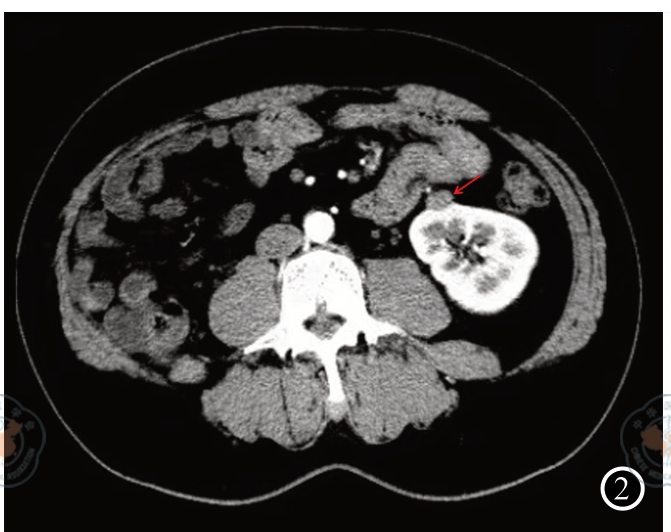

图2 孤肾合并肾炎性肌纤维母细胞瘤患者术前CT增强扫描

图7 肾炎性肌纤维母细胞瘤免疫组化(MSA×200) 注:图1中左肾下极可见一结节样密度增高影,凸向肾脏轮廓外,大小约 1.4 cm×1.1 cm(箭头所指)。图2可见左肾下极病变各期呈持续强化,边缘光滑(箭头所指)。图3可见肿瘤大小约为1.5 cm×1.1 cm×1.1 cm,切面灰白色,实性,质地中等。图4可见肾脏组织中见梭形细胞肿瘤,肿瘤细胞由纤维母细胞及肌纤维母细胞构成,细胞无明显异型性,呈束状、交织状排列,部分玻璃样变,淋巴细胞、浆细胞及组织细胞灶状聚集。图5可见肾炎性肌纤维母细胞瘤肿瘤细胞SMA呈阳性表达。图6可见肾炎性肌纤维母细胞瘤肿瘤细胞Desmin呈阳性表达。图7可见肾炎性肌纤维母细胞瘤肿瘤细胞MSA呈阳性表达